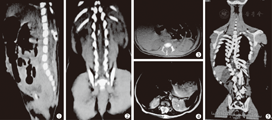

术前X线及CT检查发现脊柱畸形184例,其中椎管内骨嵴172例,椎管闭合不全162例(72%),椎板融合畸形24例(10.7%),半椎体及蝴蝶椎畸形62例(27.6%)。全脊髓MRI检查发现所有患儿均有不同程度的脊髓低位、栓系。其中腰骶部脊髓脊膜膨出33例(14.7%),腰骶部脂肪瘤46例(20.4%),脊髓空洞症175例(77.8%),骶管囊肿18例(8%)。典型病例图片见图1,图2,图3,图4,图5。